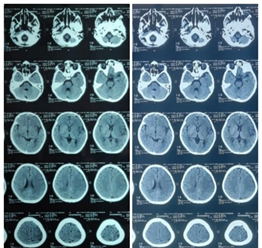

Laboratory parameters are summarized in Table 1. Complete blood count revealed neutrophilic leukocytosis with lymphopenia. Prothrombin time was 19 sec, activated partial thromboplastin time was 35.63 sec and International Normalised Ratio was 1.5. Initial ECHO showed mild LV dysfunction with ejection fraction of 41% and minimal pericardial effusion. Right coronary artery showed an aneurysm with a Z score of +2.54 and other coronaries were normal. Her inflammatory markers were elevated with D-dimer of 6.65 μg/ml (Reference range < 0.46 µg/ml) and IgG covid antibody was positive with a titre of 83.77 AU/ml (Reference range < 10 AU/ml). She was covid RT PCR negative. With a possible diagnosis of MIS-C she was started on intravenous immunoglobulin at 2 g/kg and methylprednisolone at 10 mg/kg/day. Serial echo revealed fall in EF with lowest value of 33% [Table 2] and thrombi at the left ventricular apex and interventricular septum as shown in Figure 1. In view of right fundal bleeds aspirin and heparin were withheld. Neuroimaging revealed infarct over the left frontoparietal region [Figure 2]. Child had persistent fever spikes and fall in hemoglobin and platelet counts. Bone marrow aspiration showed hemophagocytic lymphohistiocytosis. Fever work up including blood culture, urine culture, enteric fever, dengue, leptospirosis and scrub serology were negative.

Figure 2. CT Brain showing infarct involving left frontoparietal region on Day 14.

Unfractionated heparin was given at a bolus of 75 U/Kg bolus followed by 20 U/Kg/hr infusion. Child required inotropes for 13 days. On day 14, child developed right hemiparesis and CT brain revealed infarct involving left frontoparietal region [Figure 2]. She was extubated on day 20. MR angiogram revealed left MCA infarct. On day 21, oral nicoumalone at a dose of 0.2 mg/kg was started in addition to heparin under PT and aPTT monitoring. heparin was stopped on day 24. Nicoumalome and aspirin were continued. Repeat ECHO on day 27, showed no evidence of thrombi and ejection fraction was 60%. Protein C, S, Antithrombin III were normal. β2 glycoprotein [IgG & IgM] were negative. On day 37, anticoagulants were stopped as INR was prolonged. Subsequently, during hospital stay she developed malena and refractory hypotensive shock and seizures. She was reintubated. Repeat CT Brain showed subacute infarct of left frontoparietal region with hemorrhagic transformation [Figure 3]. Despite all efforts, child could not be saved.